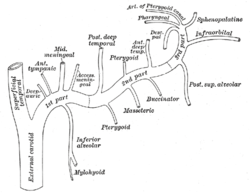

Plan of branches of internal maxillary artery. (Mylohyoid visible at bottom center.) | |

Plan of branches of internal maxillary artery. (Mylohyoid labeled at bottom center.) | |

As the inferior alveolar artery enters the mandibular foramen, it gives off a mylohyoid branch which runs in the mylohyoid groove, and supplies the mylohyoid muscle.